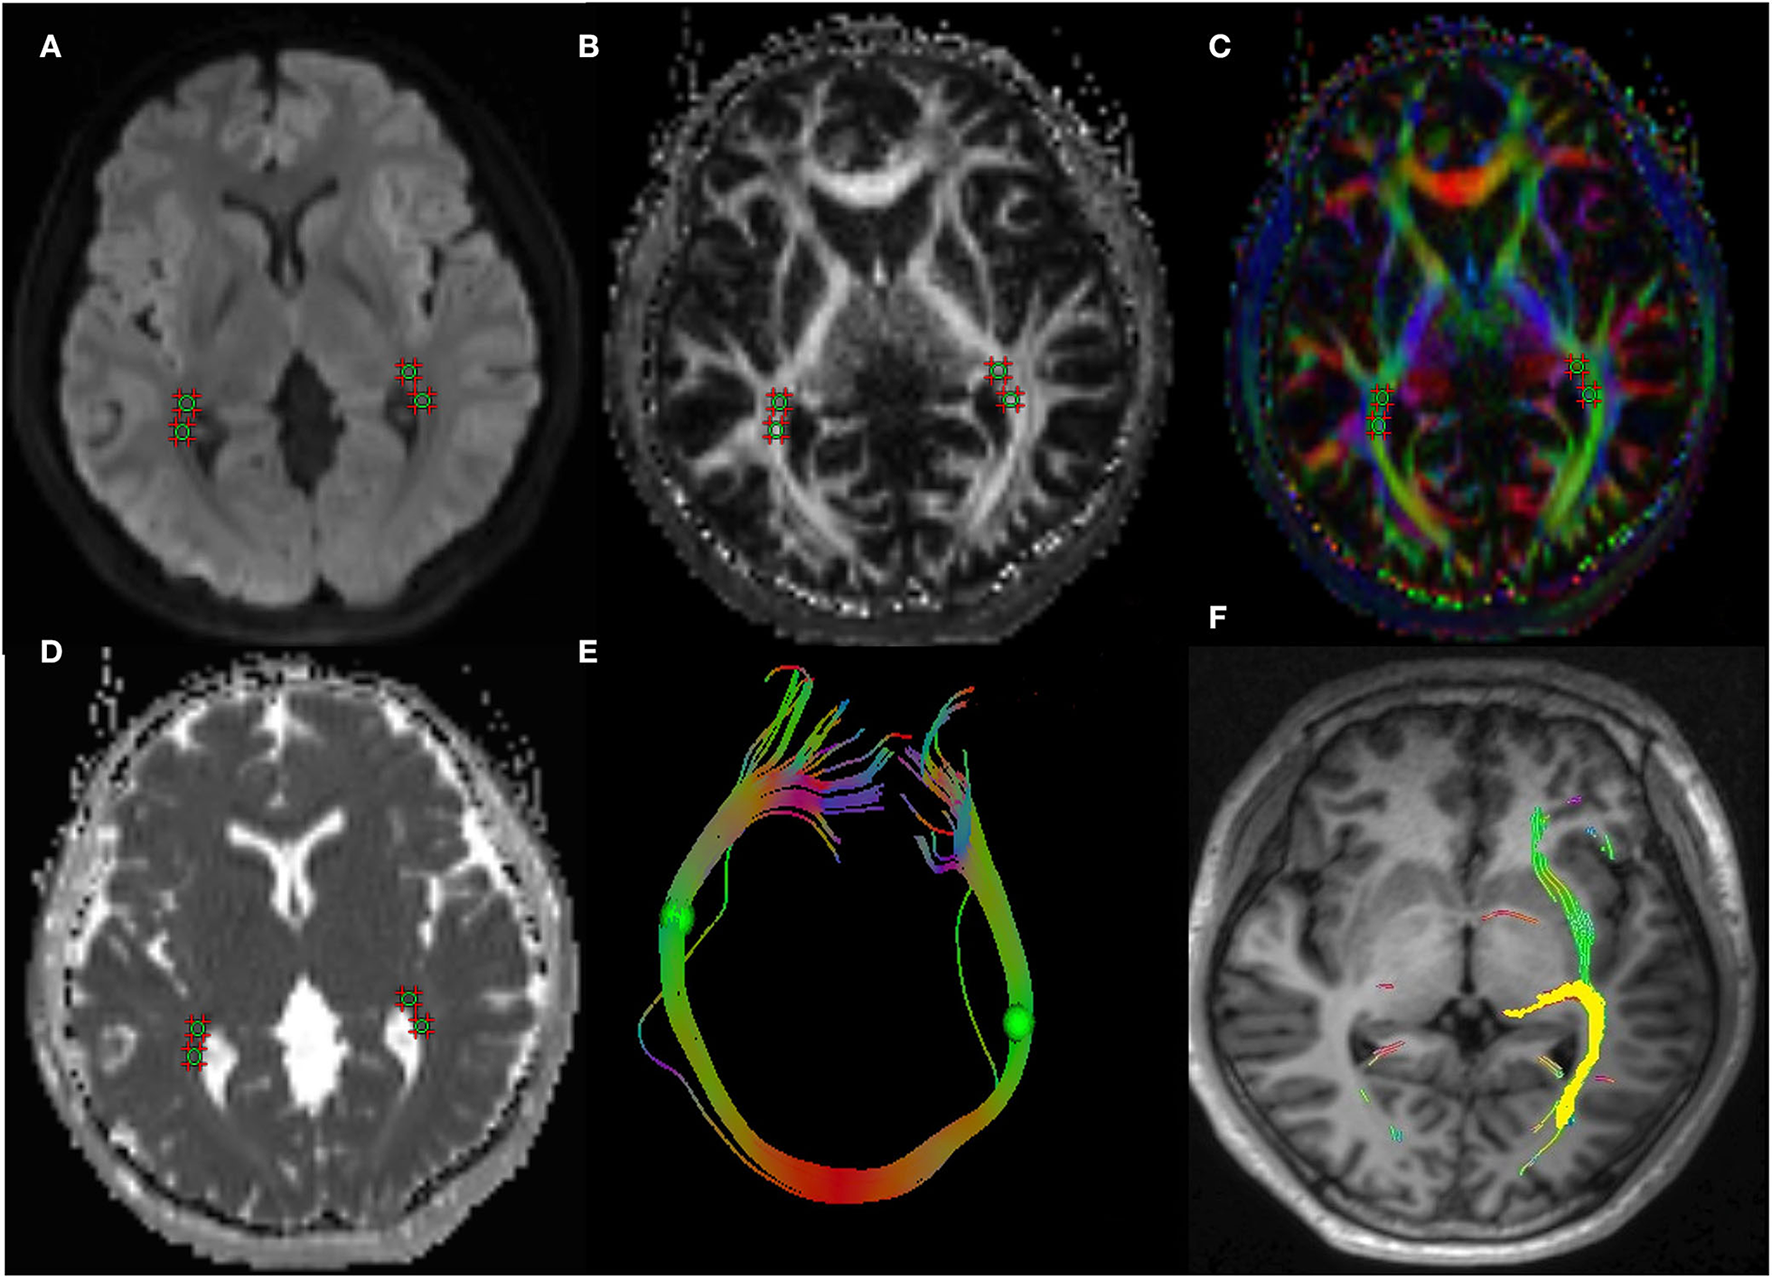

The study applied the Syngo.Via post-processing software equipped with a Siemens Prisma 3.0T post-processing workstation to measure the DTI parameters of visual pathway. The radiologist opened the TRACEW, FA, and apparent diffusion coefficient (ADC) images in MR Basic and altered TRACEW to show the LG and optic radiation (OR) at the clearest level. The region of interest (ROIs) was drawn at the bilateral LG and OR (with the TRACEW images as reference), and the diameter of each ROI was fixed at 5 mm. The FA and MD of the lateral geniculate and optic radiation were automatically computed by the software. In order to ensure the accuracy of the manually drawn ROI, we sketched the ROI anatomical site on T1WImprage continuous tracking method was used to construct fibers, and the fiber tracking began at the center of each voxel with an FA value >0.2 and ended at voxels with FA < 0.3 or the tract turning angles between two eigenvectors to be connected by the tracking were greater than 70. Then the software will automatically track and form a white matter fiber map associated with the outlined ROI. If the image is a white matter fiber map of visual pathway, it is considered that the ROI sketch is valid (Figure 1). The ROI was independently drawn by two experienced neuroradiologists who were unaware of the clinical conditions of the participants. The inter-observer agreement was calculated using the measurement results of these two observers. All DTI parameters were taken as the average value of the measurement results of the two radiologists.

Figure 1

A 43-year-old woman with TAO. Schematic diagrams for measurements of visual pathway on DTI. Figure (A–D) showed the axial TRACEW, FA maps, color FA, and ADC. (E) showed an “open-loop structure” consisting of bilateral optic radiation white matter fibers and splenium of corpus callosum. (F) showed the visual pathway white matter fiber tractography, the yellow stands for the track result of LG, it shows the subcortical pathway reaching primary visual cortex through the optic radiation. A circle region of interest was manually set on LG and OR, with careful avoidance of surrounding tissues. Fiber tractography was then carried out to confirm correct placement of ROI. TAO: thyroid-associated ophthalmopathy, DTI: diffusion tensor imaging, FA: fractional anisotropy, ADC: apparent diffusion coefficient, LG: lateral geniculate, OR: optic radiation.